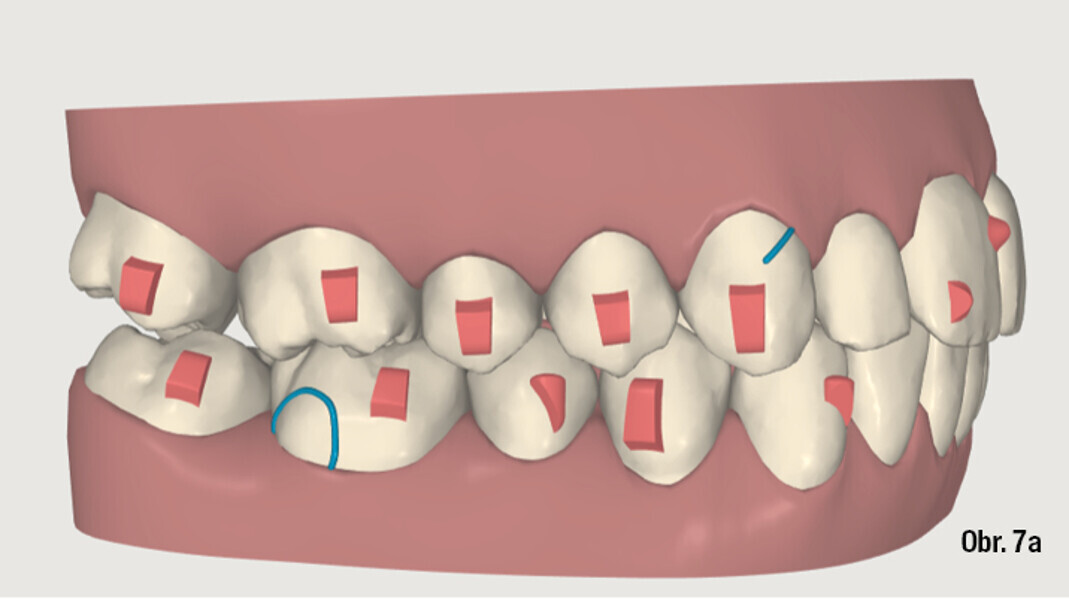

Distalizace horních molárů pomocí alignerů a cyklických sil